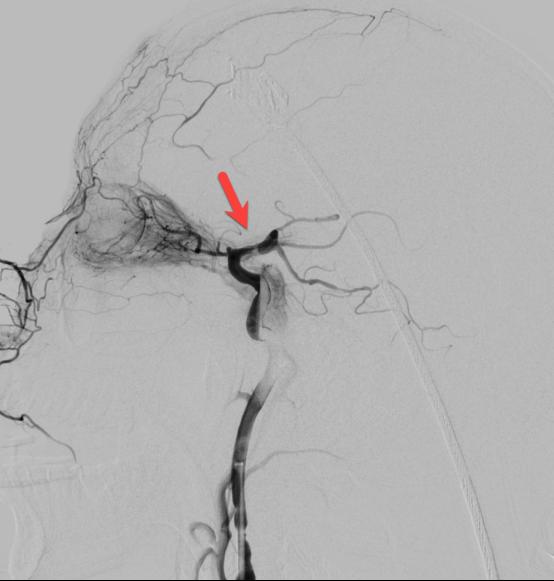

在转运的过程中,患者症状持续加重,完全失语、右侧肢体全瘫同时意识逐渐模糊。糟糕,一定是左侧颈内动脉闭塞后血流缓慢继发颅内血栓形成。时间就是大脑,为挽救李大哥的生命,民航总医院卒中团队高效运作起来,神经内科、血管介入科、麻醉科迅速完成了患者的转运、麻醉及造影。如术前所料,患者左侧颈内动脉C6段闭塞(图4、5),左侧大脑中动脉M2段血栓形成(图6)。一个一个环环相扣的动作,一个一个精细无间的配合,血管介入科团熟练的完成了取栓支架就位(图7)、取出大脑中动脉血栓、植入颈内动脉支架(图8)等一系列操作,成功的开通了血管,恢复了颅内的血流(图9、10)。

图8

图9

图10